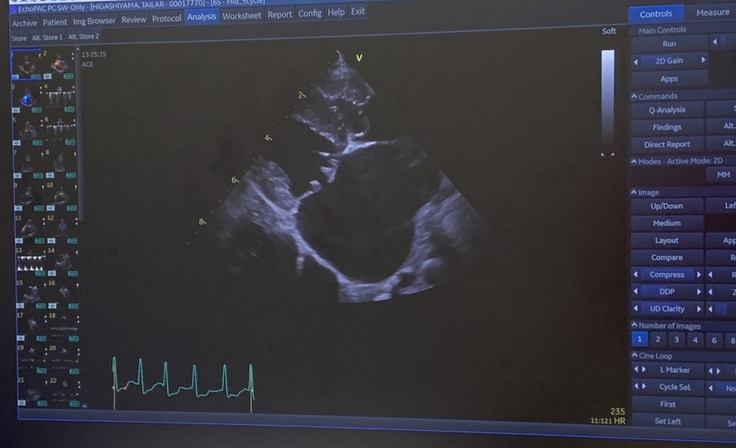

心臓が以前の検査と比べるとかなり肥大化していてとても危ない状態。

心臓は更に肥大化している。心拍数は常に250。通常は100前後。

どちらも通常の2.5倍です。

僧帽弁が閉じきらずに血液が逆流すると、

左心房(肺から血液を受け取る部屋)に強い圧力がかかります。

時間が経つとその負担で左心房がどんどん拡大し、

電気信号の伝わり方が乱れてしまい、

→ 心房細動(しんぼうさいどう)や心房粗動などの不整脈が起こります。

⚡ 不整脈(心拍数250あります)

心拍数が250/分というのは、通常の2.5倍以上で、

これは明らかに**重度の頻脈性不整脈(例:心房細動または心房粗動)**の状態です。

心臓が速すぎて、十分に血液を送り出せない。特に拡大した左心房では、ポンプとしての力が落ちて

→ 肺からの血液が心臓に戻れなくなる(肺うっ血)

→ 肺に水が溜まり、呼吸困難・肺水腫が起きています。